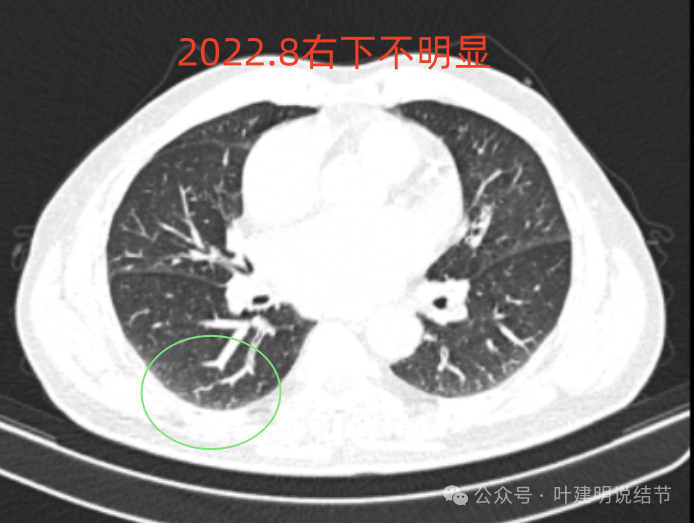

再看2022年8月复查时AI报告找出来的影像:

多是微小实性结节,主要的仍是右上与左下的这两处,较3月时无明显变化。而右下原来似有微小结节处这次并不明显。